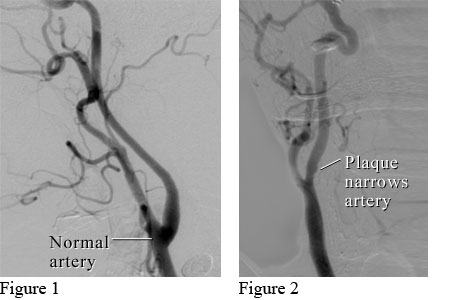

Angiograms of a normal neck artery and a neck artery narrowed by plaque

Figure 1 shows an angiogram (a type of X-ray) of a normal neck artery (carotid artery) with smooth walls. Figure 2 shows a narrowed carotid artery with ulcerated plaque (the surface of the plaque is irregular and broken) that is the source of clots. If clots travel to the brain and block blood flow, they can cause a TIA or stroke.